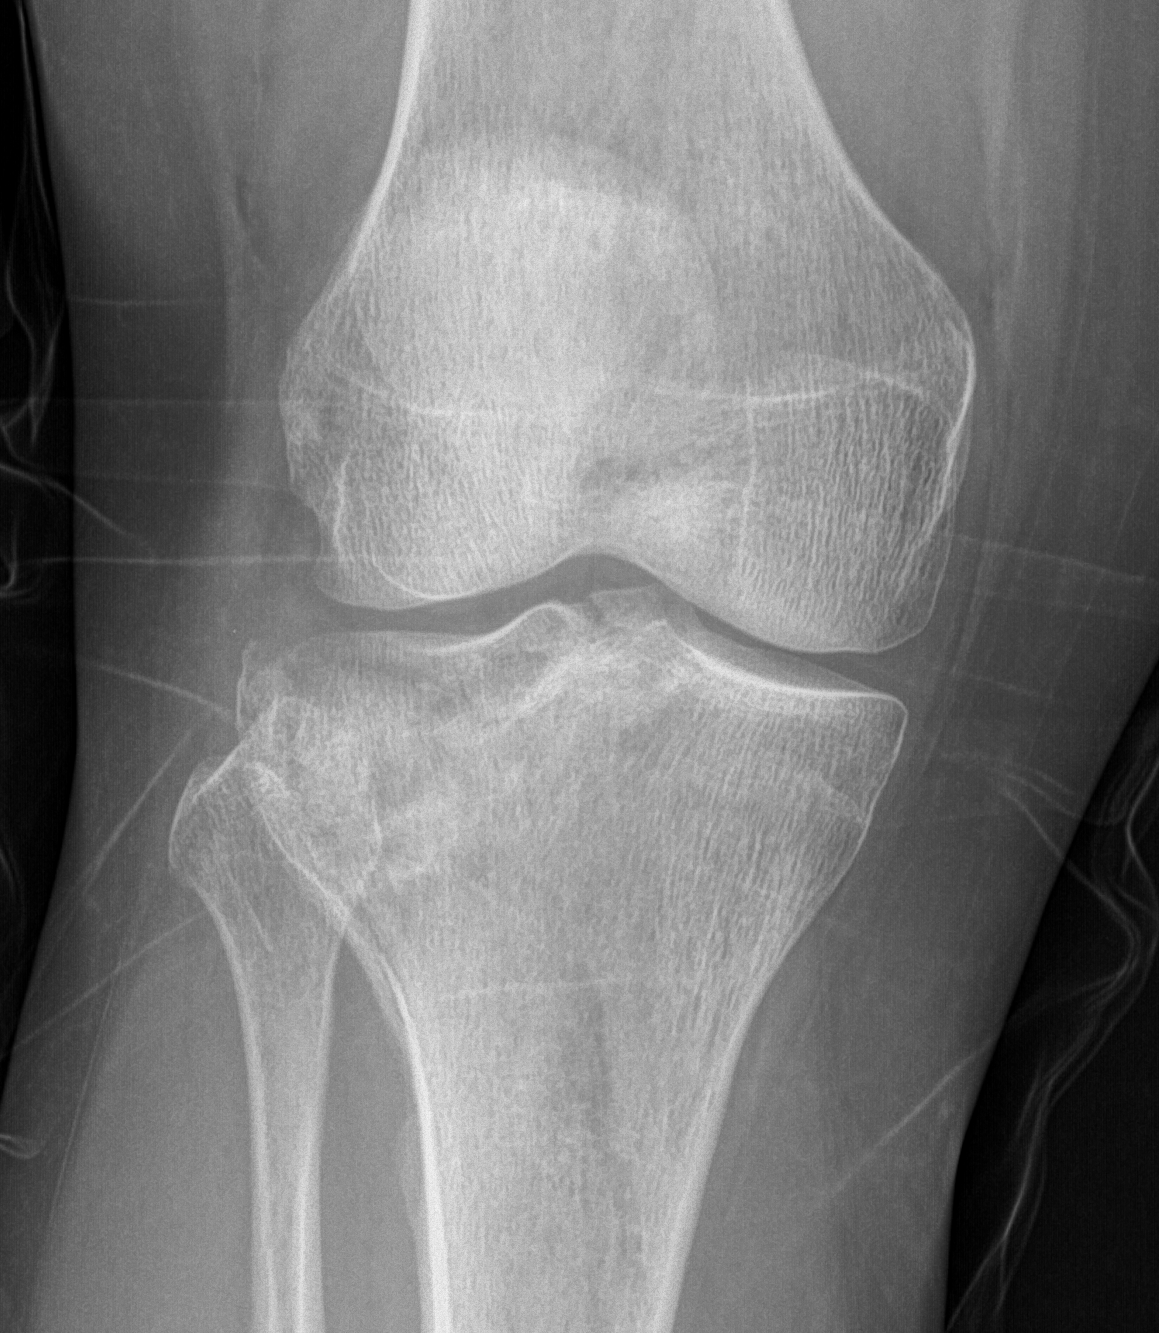

Schatzker Classification

I. Lateral Spilt

- seen in young patient

- lateral meniscus can be incarcerated in fracture

II. Lateral Split Depression

- often seen in young patients with high energy injuries

- vary in severity

III. Lateral Depression

- central depression usually seen in elderly

- have to create lateral cortical window in order to elevate fragment

IV. Medial plateau & intercondylar eminence

- high velocity injury associated with ACL / LCL / CPN injury

- can be low injury / osteoporotic and often unreconstructable

V. Bi-condylar + intact metaphysis

- unstable

- requires ORIF

VI. Bi-condylar + metaphyseal fracture

- fracture separating metaphysis from diaphysis

- highest incidence of vascular injury